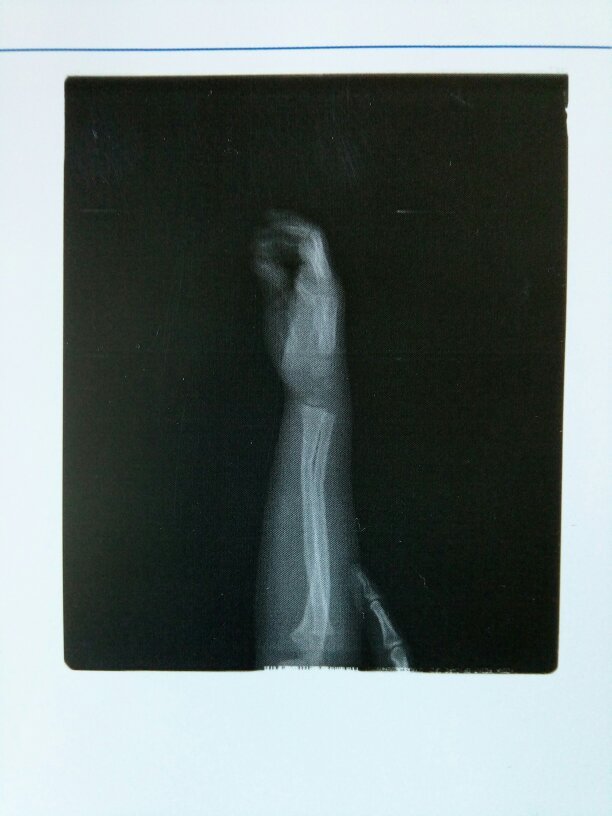

5岁宝宝右手尺桡骨远段青枝骨折 点击展开 匿名用户 2016-08-22 15:18 为您推荐: 其他回答 见于老年妇女、儿童及青年.骨折发生在桡骨远端2~3cm范围内.常伴桡腕关节及下尺桡关节的损坏 祈康胜_lHWO 2016-08-22 15:34 相关问题 孩子右手尺桡骨骨折 术后手有水肿 请问有什么办法可以消肿 跪谢 左桡骨远端青枝骨折要多久才能好? 如何处理左桡骨远端青枝骨折